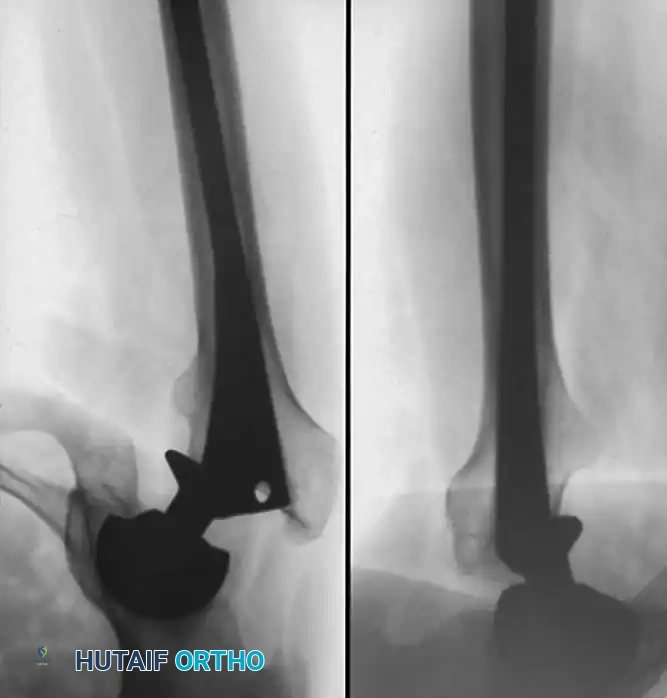

Associated Surgical & Radiographic Imaging